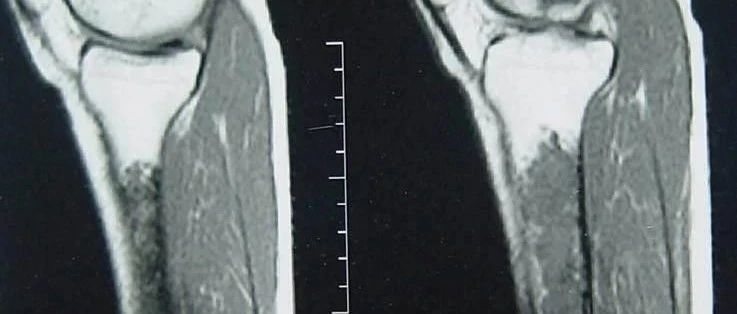

点击标题下「蓝色微信名」可快速关注文章来源: 中华骨科杂志,2020,40 (15): 979-987作者:孙昆昆 谢璐 郭卫 孙亦雯 孔方舟 沈丹华摘要 目的探讨透明细胞软骨肉瘤(clear cell chondrosarcoma,CCCS)的临床表现、影像学特点、病理组织学特征、诊断陷阱、治疗以及预后。方法回顾性分析2010年1月至2020年1月23例收治并手术治疗的透明细胞软骨肉瘤患者资料,其中男21例,女2例;年龄(45.78±16.19)岁(范围:27~72岁)。21~40岁8例(35%),41~60岁10例(43%),61~80岁者5例(23%)。发病部位股骨8例,骨盆7例,胸腰椎4例,骶骨3例,胫骨1例。术前穿刺及术后大体标本用10%中性福尔马林固定,5%硝酸脱钙处理,石蜡包埋,行苏木素-伊红(hematoxylin and eosin,HE)染色及免疫组织化学染色(envision法),收集术前影像学表现及临床症状,术后显微镜下病理组织学表现及免疫表型,归纳总结透明细胞软骨肉瘤的临床、影像学及病理形态学特点。...